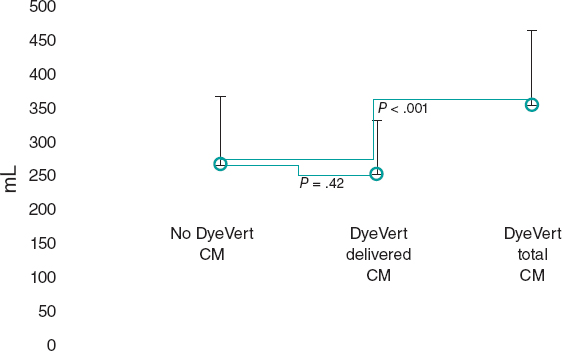

5. When the clip remains perpendicular on the TV, the GC clockwise rotation will move the clip towards the septal position. The GC counterclockwise rotation will move it towards the lateral region. The stabilizer advancement will bring the clip closer to the A-S commissure. After retraction, it will pass to the P-S commissure. This will allow complete range of motion and guarantee the correct location of the grasping (figure 5).

Figure 5. A: transesophageal echocardiogram in 3D zoom mode; periprocedural frontal view. The guide catheter can move inside the right atrium towards the aortic valve by advancing the entire system (red arrow) or towards the posterior leaflet by retracting it; the movement towards the septum (blue arrow) is possible through clockwise rotation of the guide catheter, and towards the right ventricle free wall through counterclockwise rotation. B: explanted heart, anatomic view. A, anterior; Ao, aorta; P, posterior; S, septal; CS, coronary sinus.